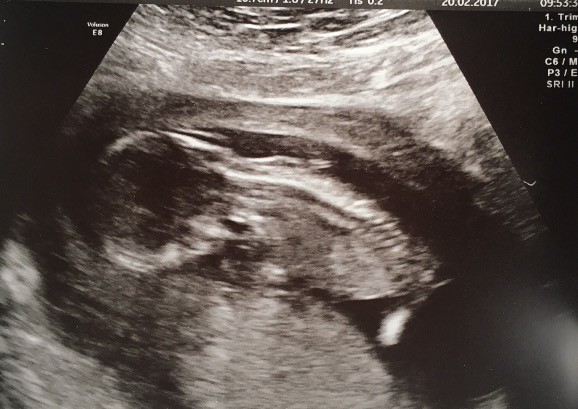

Dixiechick1991 · 20/02/2017 18:03

Hello,

Hi ladies! Had my scan this morning, peanut is healthy and happy but a little awkward- dedided to flip over and stay face down no matter how much coughing, walking and wiggling I did! 😂🙊 need further bloods at my next midwife appt due to not being able to do screening tests but other than that, honestly a weight has been lifted!! X

lovely scan!

Lovely scan charli!

Ah Charli & Ruth, really glad your scans went well Smile